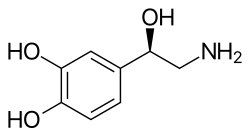

- Norepinephrine